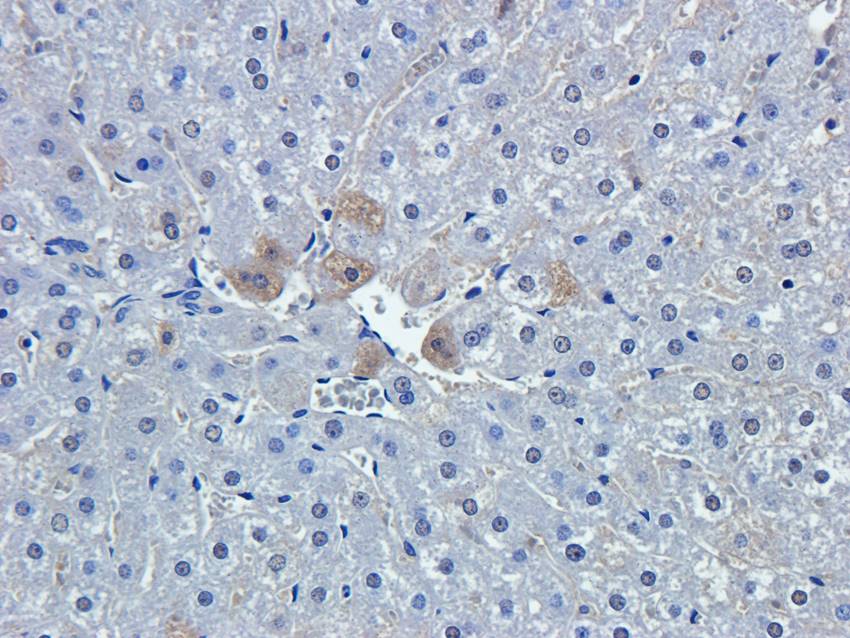

IHC staining of FFPE human brain with Ubiquitin antibody (clone PBQN-1). Required HIER: boil tissue sections in pH9 10mM Tris with 1mM EDTA for 10-20 min followed by cooling at RT for 20 min.